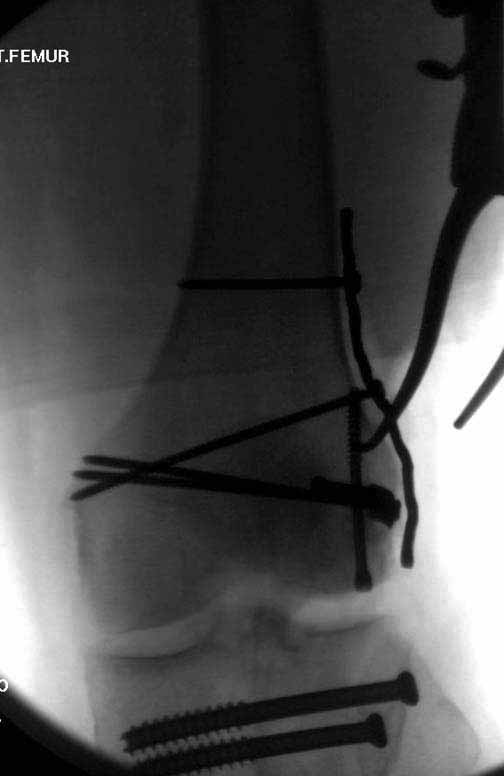

Антеградное штифтование не очень годится при переломах типа C3, когда есть многооскольчатость именно суставной поверхности. А при переломах типа C1 и С2, т.е. и в обсуждаемом случае тоже, он как раз вполне оптимален. На межфрагментарную компрессию как-то не приходилось так драматически полагаться при интрамедуллярном остеосинтезе, результаты хорошие без нее были.

В этой терминологии мы, получается, создавали компрессию встречными спицами с упорами или reduction clamps, а потом вполне обходились запирающими винтами как позиционными. Бывает, проводим 1-2 спонгиозных винта 6,5-8 мм - вот они вполне компрессирующие.

И уже лет шесть мы используем возможность ввести в дистальное овальное отверстие 3 винта, которые именно запираются в этом отверстии, не люфтят, а обеспечивают угловую стабильность - см картинку.

Получается и стабильно, и очень дистально, нижний край отверстия в 3 мм от дистального конца гвоздя.

В приложении пример недавней операции, C3, открытая репозиция, фиксация мыщелков спицами и винтами, ретроградный синтез большеберцовым гвоздем 10,5 мм диаметром, винты 5 мм.

Позволю себе напомнить коллегам ещё раз, что являюсь сторонником антеградного остеосинтеза при переломах дистального эпиметафиза бедренной кости. Такая приверженность основана не на преимуществах внесуставного введения стержня или большем проценте положительных результатов. Она основана на возможности обеспечить блокирование на минимальном расстоянии от суставной поверхности в нескомпрометированной кости и, таким образом стабилизировать максимально низкие переломы. В приведенном Вами случае самый дистальный из блокирующих винтов проведен на расстоянии более 2 см от конца стержня. Из-за того, что к стержню присоединяется кондуктор, на стержне теряется 1-1,5 см его длины, где можно было разместить отверстия для блокирования. И что более важно, вместе с потерянной для этой цели длиной стержня утрачивается для размещения блокировочных винтов, пожалуй, самая ценная часть дистального эпиметафиза бедренной кости. Проблемы дистального блокирования в разных плоскостях, локализации точки ввода стержня при антеградном остеосинтезе – это всё решаемые технические проблемы. Но антеградный остеосинтез низких дистальных переломов бедра при адекватном блокировании в нескомпрометированной кости обеспечивает решение стратегической задачи – стабильный остеосинтез и возможность нагрузки.

В приведенном Вами случае самый дистальный из блокирующих винтов проведен на расстоянии более 2 см от конца стержня.

На этом большеберцовом стержне центр ближайшего к кондуктору отверстия в 14 мм от конца. И пример был про то, что пластина тут, скорее всего, была бы не худшим выбором.